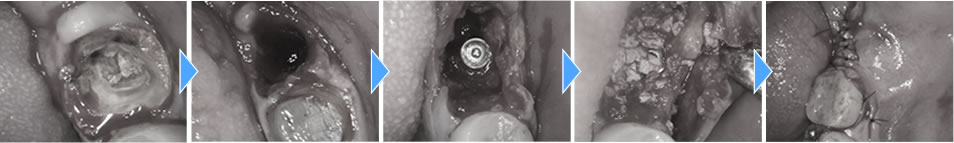

まず歯を抜き、中の膿を綺麗に取り除いた後に即時でインプラントを埋入し、骨の無くなってしまっている場所に骨造成を行いました。こちらは減張切開を行い、創の完全閉鎖をしました。

固定もしっかりと得る事ができ、4ヶ月置いて進めていく予定でしたが、途中で1つ前の歯も痛みだしたため、やはりこちらの歯も抜いてインプラント治療を行いたいという事になりました。